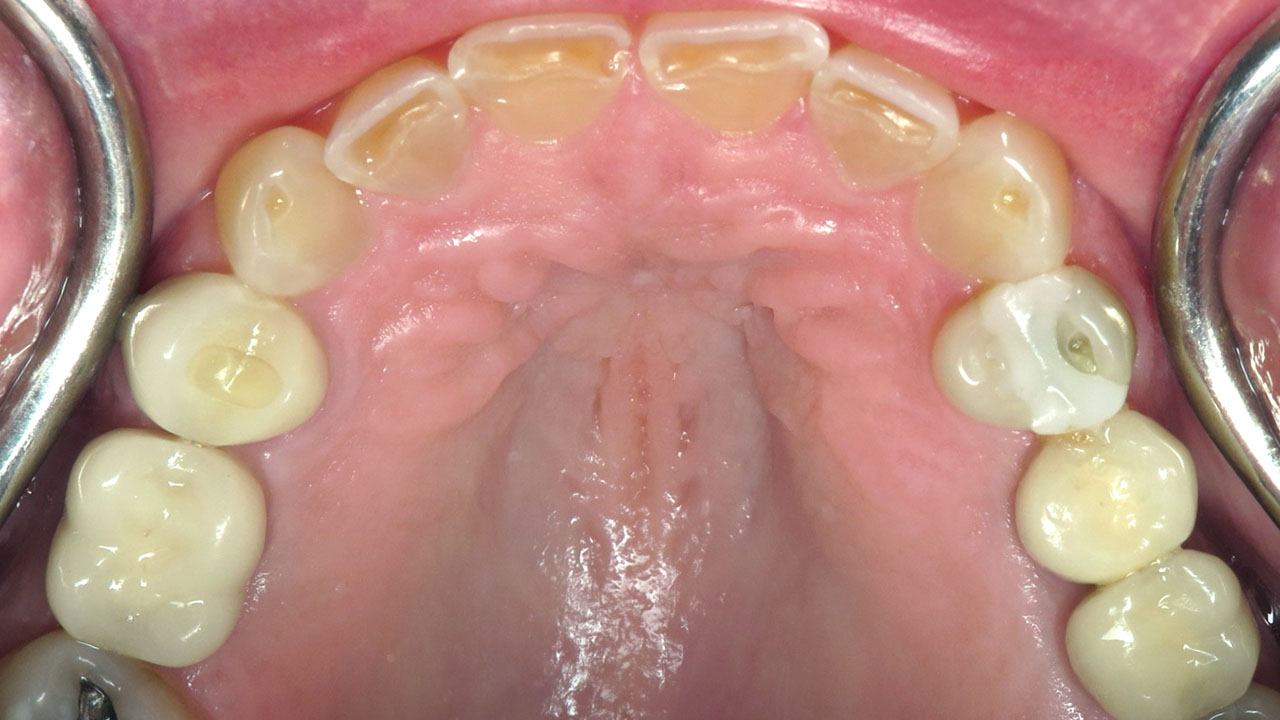

The patient had been diagnosed with sleep apnea and experienced severe tooth grinding. She noticed her front teeth becoming progressively thinner and sharper and was concerned about continued wear and damage.

Conservative composite bonding to rebuild and protect the worn edges of the upper and lower front teeth.

Composite bonding on seven upper teeth and eight lower teeth.

This patient had been diagnosed with sleep apnea and experienced significant tooth grinding. Although she wore a nightguard, she noticed she was also grinding during the day while working. Over time, the constant pressure had worn the edges of her front teeth very thin and sharp.

Several treatment options were discussed, including orthodontics with crowns on the front teeth or full mouth rehabilitation. The patient understood the long-term nature of the problem but was not ready for that level of treatment.

Instead, conservative bonding was used to rebuild the worn edges of the upper and lower front teeth. The treatment protected the exposed dentin and improved comfort and appearance while preserving future treatment options.